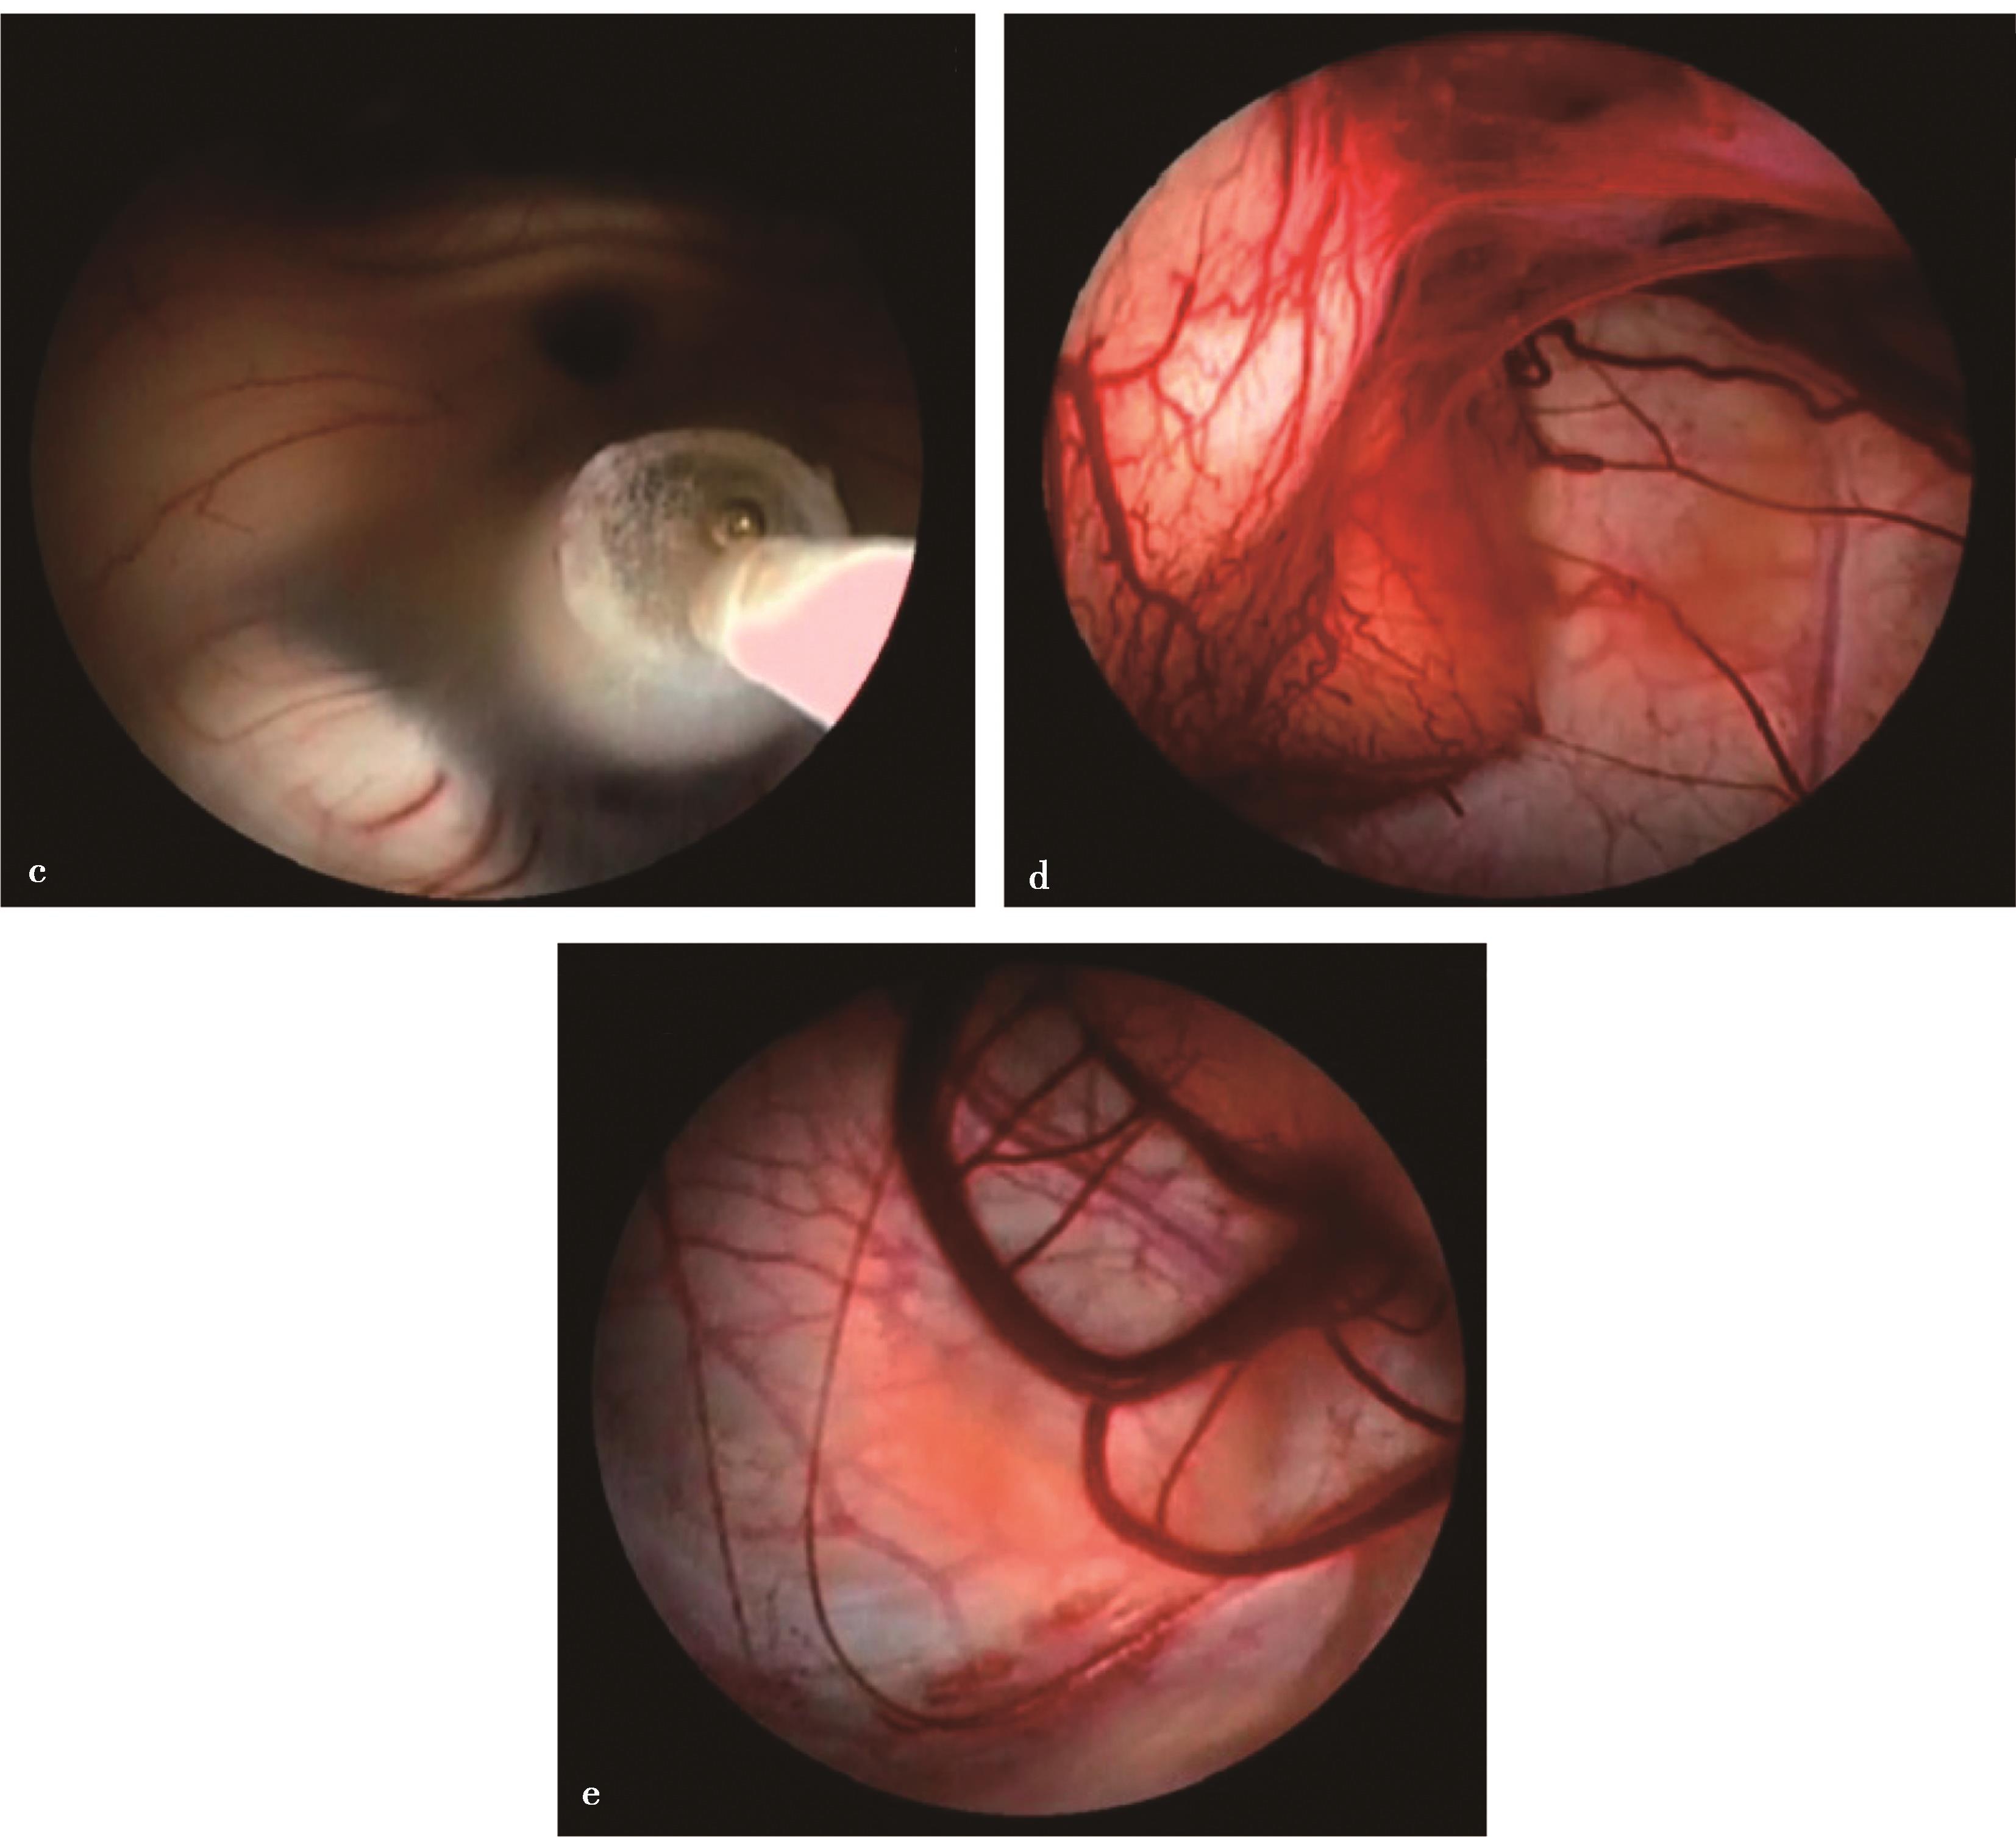

图3-1-1-4 感染后脑积水内镜下探查所见

a.脑室壁上的菌斑;b.脑室内结核所致干酪样坏死物;c.脑室内真菌感染;d.第四脑室内囊虫